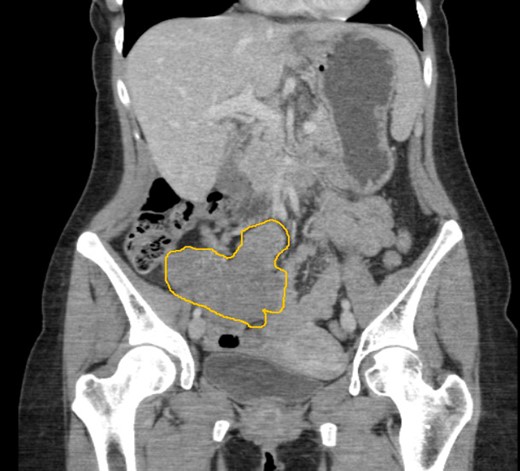

An ultrasound scan (USS) was performed and a 9 cm mass was demonstrated. A subsequent computer tomography (CT) scan confirmed the mass (Fig. 1) and raised the possibility that the mass may be a small bowel neuroendocrine tumour. The mass reported as separate from the appendix and caecum and no evidence of appendicitis. On the following day, the images were presented, the case was discussed at the colorectal multi-disciplinary team (MDT) meeting and a collective decision was made to perform a magnetic resonance imaging (MRI) scan which the patient underwent the following day. MRI was performed to specifically define the anatomy of the small bowel and its relation to the mass, as this was not clear on CT imaging. Ultimately, the MRI demonstrated a mass with vascular pedicle arising from the inferior aspect of the right hepatic lobe and the appearance raise the possibility of an exophytic liver lesion which has undergone torsion (Fig. 2). She was taken for a diagnostic laparoscopy the next day however given the size of the mass and the slim body habitus of the patient, a decision was made to convert to lower midline mini laparotomy.

CT imaging demonstrating a 9 cm lesion in the right iliac fossa, displacing adjacent small bowel.